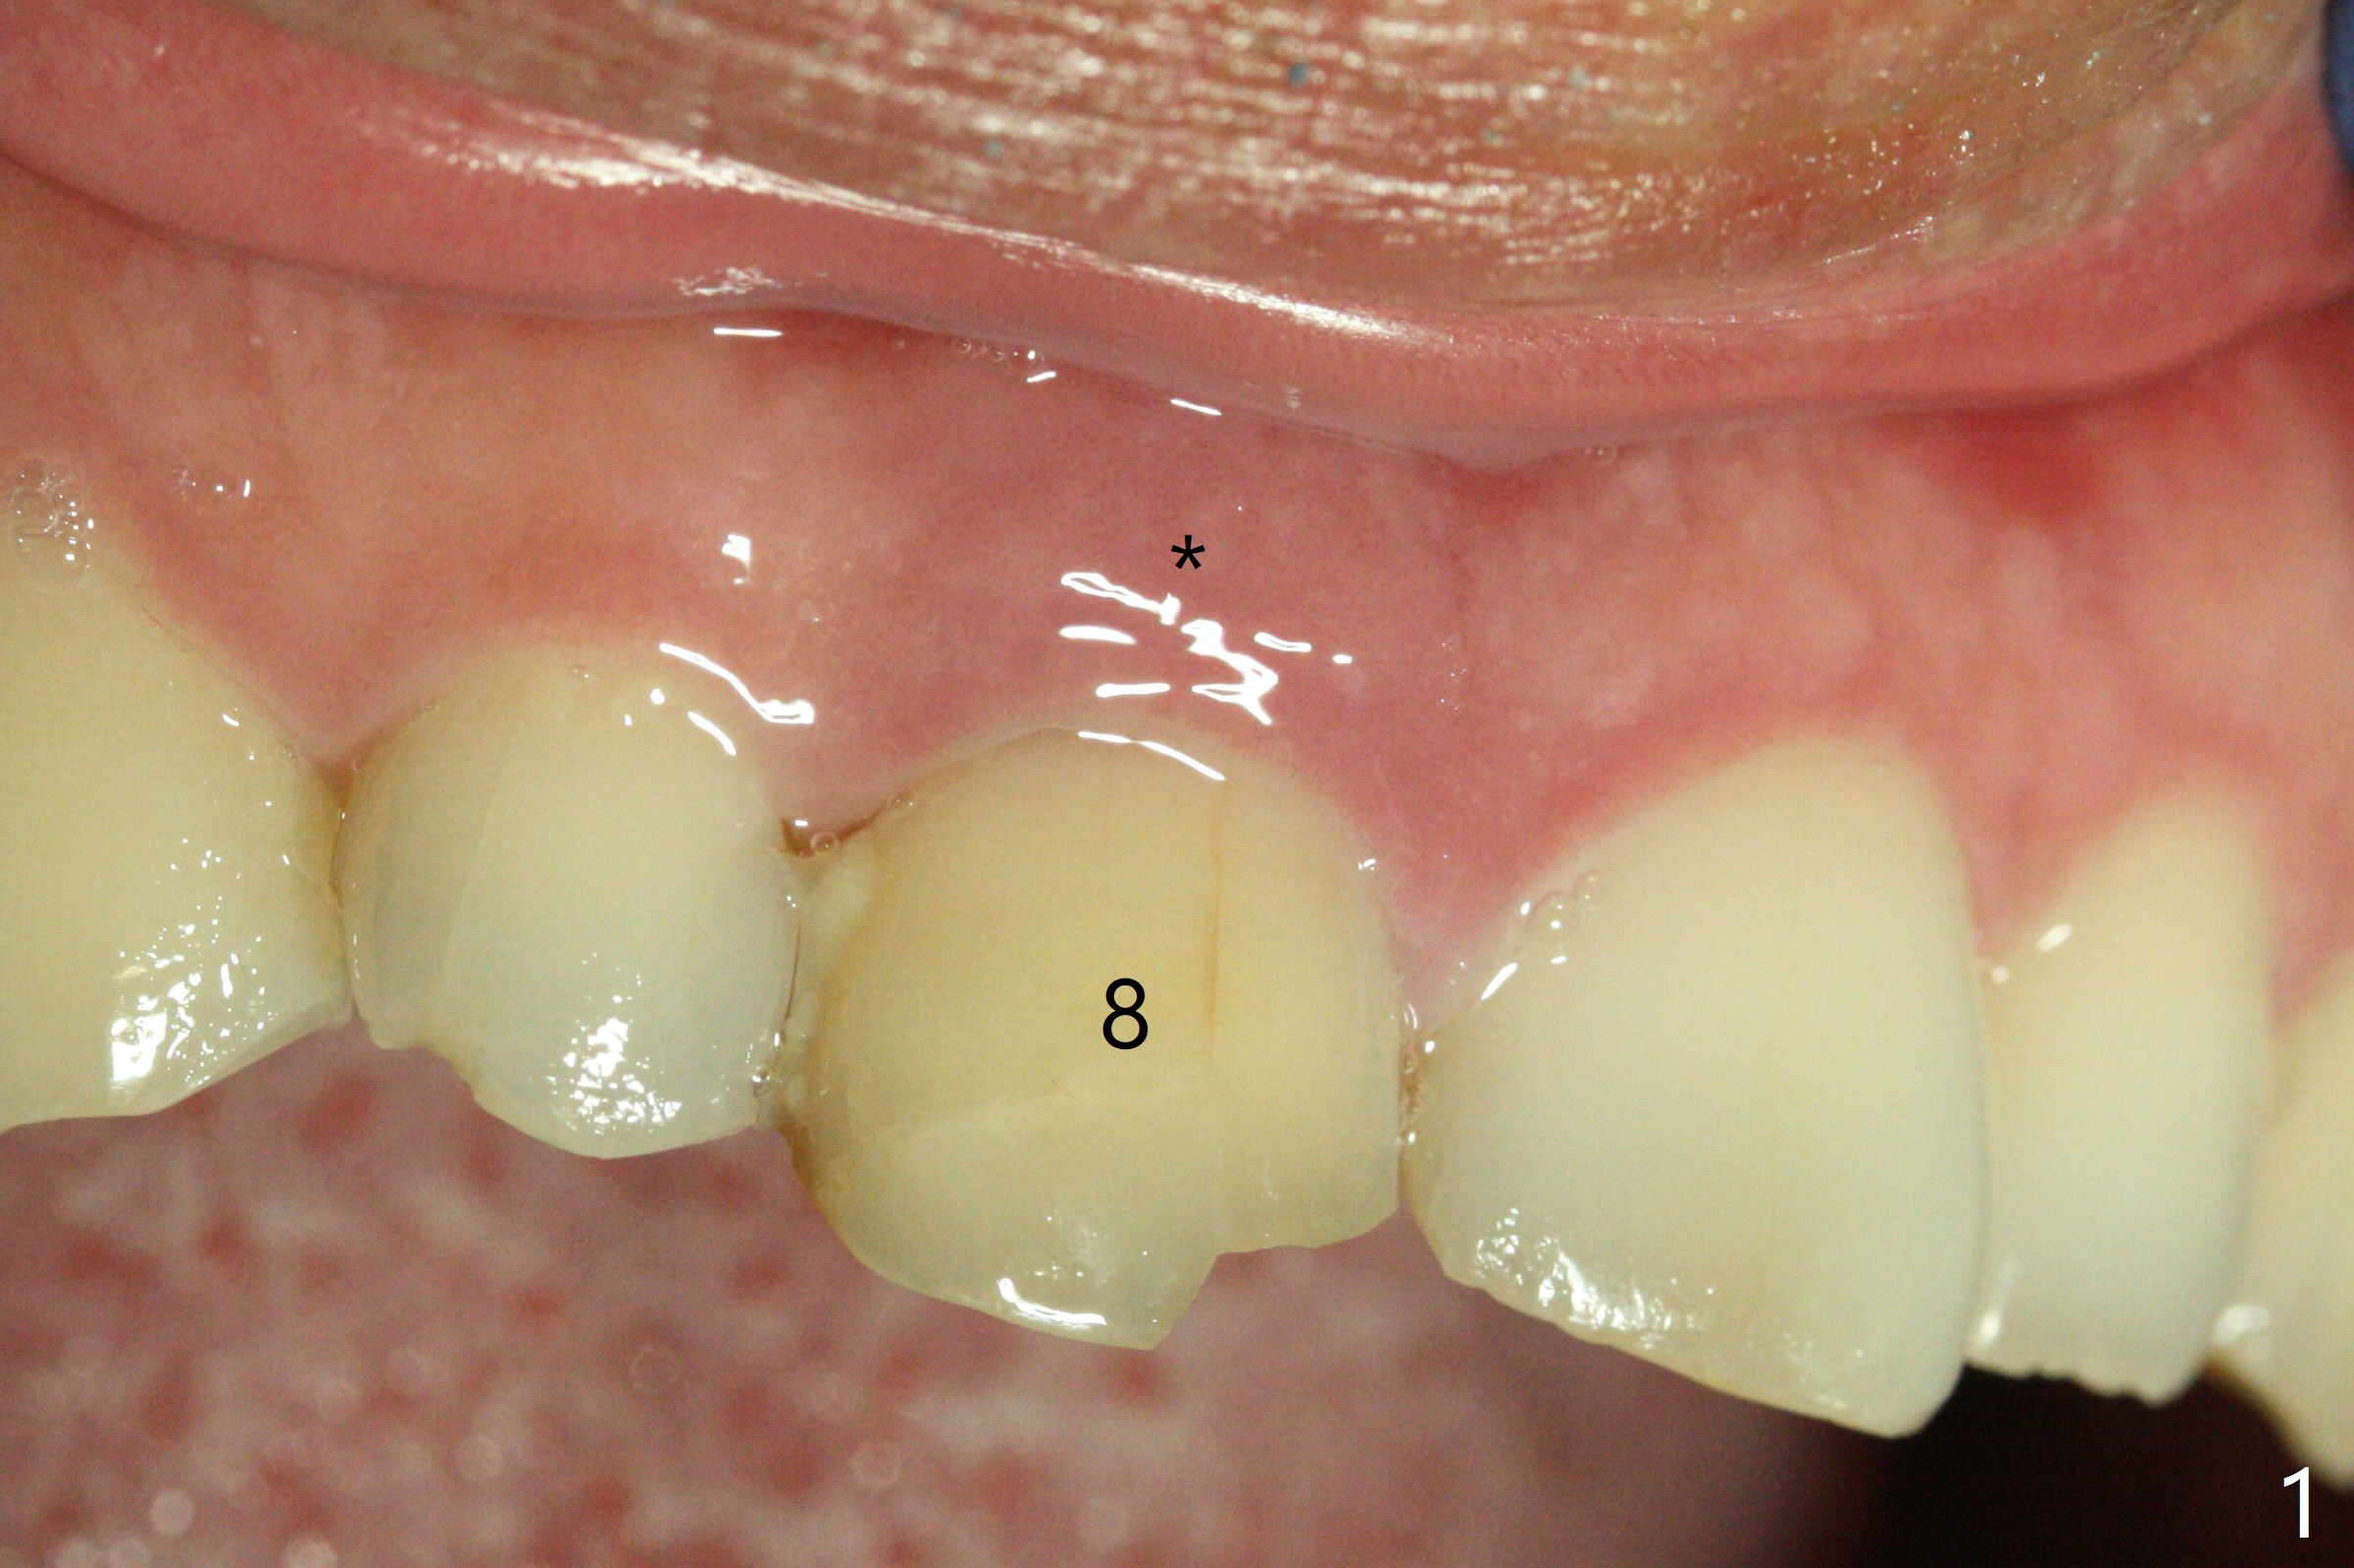

The buccal gingiva at #8 is erythematous (Fig.1: *), which is associated with the tooth fracture line (Fig.2 with granulation tissue: *). The buccal plate remains intact. Osteotomy is initiated in the palatal wall of the socket (Fig.3,4). The initial osteotomy depth is 16 mm (Fig.5); the trajectory is going to be adjusted as shown by arrows. The trajectory improves when a 3.8x15 mm dummy implant is placed (Fig.6). The definitive implant (3.8x16 mm) appears to be placed at an appropriate level (Fig.7). A 4.5x3 mm temporary abutment is inserted for an immediate provisional. As routine, Vera Graft is placed in the buccal gap. The buccal gingival erythema reduces without tenderness 1 week postop (Fig.8). Although the provisional is unstable, there is no bone loss 2 months 20 days postop (Fig.9). Because of the loose provisional (partial detachment from the underlying temporary abutment), impression is taken earlier (3 months postop, Fig.10,11). Due to the pointed abutment tip, the crown is redone 3 times. By the time of cementation (nearly 5 months postop), the socket appears to have healed (Fig.12).